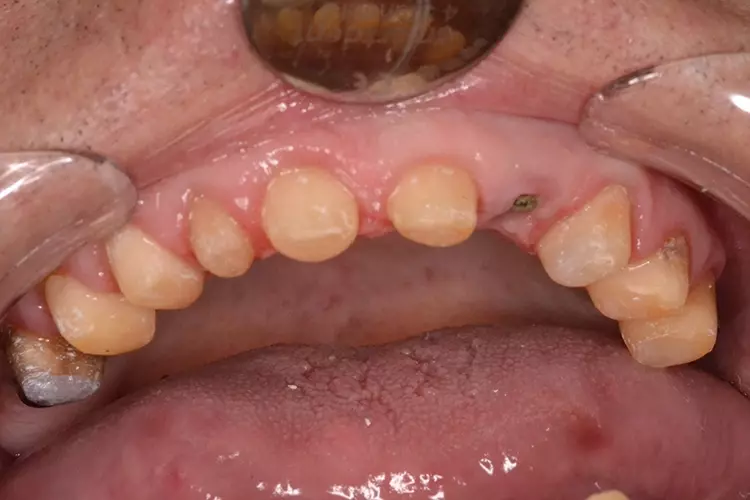

Bei dem heute 49-jährigen Patienten wurde seit Kindertagen versäumt, die Ober- und Unterkieferzahnbögen kieferorthopädisch auszurichten. Der Patient leidet seitdem stark unter seinen Zahnfehlstellungen.

Die Fraktur des stark elongierten Zahnes 21 war für den Patienten der Ausgangspunkt, sowohl die Front des Ober- als auch des Unterkiefers prothetisch überarbeiten zu lassen. Dabei wurde der frakturierte Zahn 21 durch ein navigiert eingesetztes Sofortimplantat ersetzt, während die verschachtelt stehenden Zähne 12 und 42 durch eine Brückenversorgung korrigiert wurden (Abb. 4a-j).